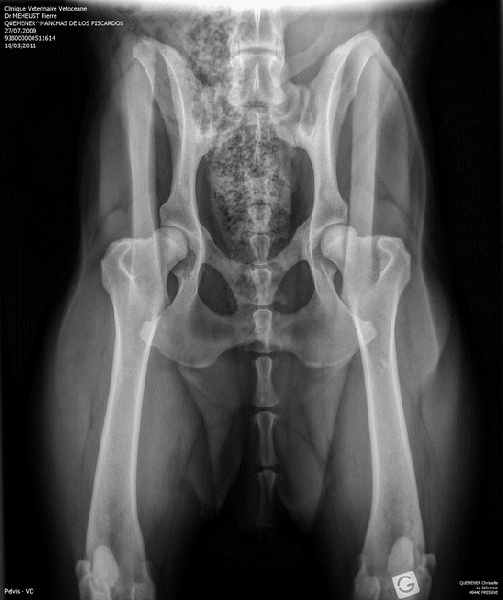

Manchas est indemne de dysplasie coxo fémorale .... dys AA